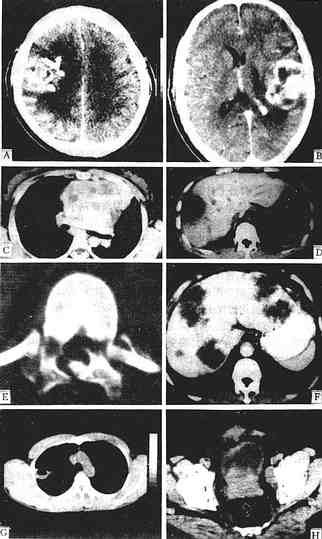

图1-2-6 CT图像

少支胶质细胞瘤增强,右额、顶叶有一较大不规则肿块,强化不均,周围有低密度水肿

星形细胞瘤 增强,左额顶叶有一不均匀强化肿块,不规则,内有未有强化的低密度区,周围有低密度水肿区,中线结构右移

胸腺增生 平扫胸腺区有一分叶状密度均一病灶,仍呈胸腺状,主动脉受压右移

肝脓肿 平扫,肝右叶有一低密度灶类圆形,中心部密度更低为脓腔,周边为脓肿壁呈“双边征

腰椎骨折 平扫,椎弓多处中断,椎管变形,其内可见碎骨片

肝转移癌 增强,肝左、右叶多个大小不一、不规则低密度灶,周边有细的强化环围绕

肺脓肿 平扫,右上叶有一空洞性病灶,内壁光滑,并见气液平面,胸部X线片曾疑肺癌

前裂腺癌 平扫,前列腺分叶状增大,并向膀胱内突入